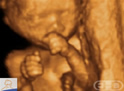

| Compre AgoraDe The Biology of Prenatal Development. |

Roteiro: ここで初めて 性差による発達の違いが現れます たとえば 女の胎児の顎の動作は 男の胎児より頻繁です |